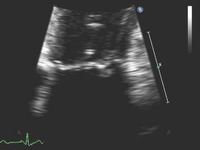

Regurgitação mitral

Corte apical de 4 câmaras de regurgitação mitral 1-2+ posterior

Do acervo de Samir Kapadia e Mehdi H. Shishehbor